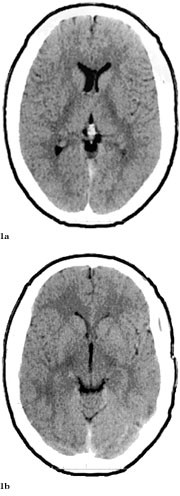

Pasienten ble overflyttet til Namdal Sykehus 6.6. Han var somnolent, desorientert og gav stereotype svar. Han hadde ingen fokale utfall. På mistanke om herpes simplex-encefalitt ble det iverksatt behandling med aciklovir 3 ⋅ 750 mg intravenøst, i tillegg fenytoin 2 ⋅ 250 mg intravenøst mot symptomatiske epileptiske anfall. Dagen etter ble pasienten soporøs. EEG var preget av en generalisert langsom aktivitet, delvis i form av bilateral synkron, rytmisk deltaaktivitet (frontal intermittent rhythmic delta acitvity, FIRDA). CT viste symmetriske forandringer i basalgangliene og basale deler av cerebrum som var ødematøs (fig 2a, 2b). En ny spinalvæskeprøve, tatt 8.6., viste 17 celler. En CT fra 9.6. viste progredierende forandringer (fig 3).

Dessverre hadde vi ingen mulighet til å få utført MR og obduksjon. Likevel er en akutt demyeliniserende encefalomyelitt mindre sannsynlig på grunn av at sykdomsutviklingen ikke kom helt akutt, men var gradvis innsettende i løpet av ti dager. Dessuten hadde man ikke fokale eller multifokale motoriske eller sensible utfall (10, 13). CT-funn viste progredierende, symmetriske forandringer som gav hypodensitet først i basalganglier og senere generelt, men hele tiden mest i basale deler av storehjernen og i de limbiske strukturer (fig 1 – 3). Retrospektivt aner man allerede ved første CT-undersøkelse (fig 1b) små hypodense områder ut for 3. ventrikkel på hver side lavt i basalgangliene. Disse funnene tyder heller på en atypisk encefalitt enn på en akutt demyeliniserende encefalomyelitt og korresponderer med de kliniske funn av hukommelsesproblemer og personlighetsforandringer. Pasienten fikk terminalt sentral respirasjonsstans, noe som kan tyde på hjernestammeaffeksjon.